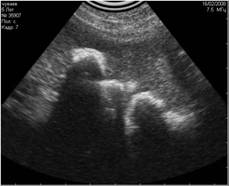

![]() |

Рис.13. Истинная тень, испускаемая каловыми массами в кишечнике. В данном случае имитирует асцит. |

Рис. 14. УЗИ предыдущего животного. Изменение угла наклона датчика помогает избежать ошибки. |